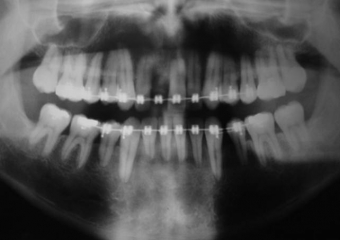

Raio X inicial